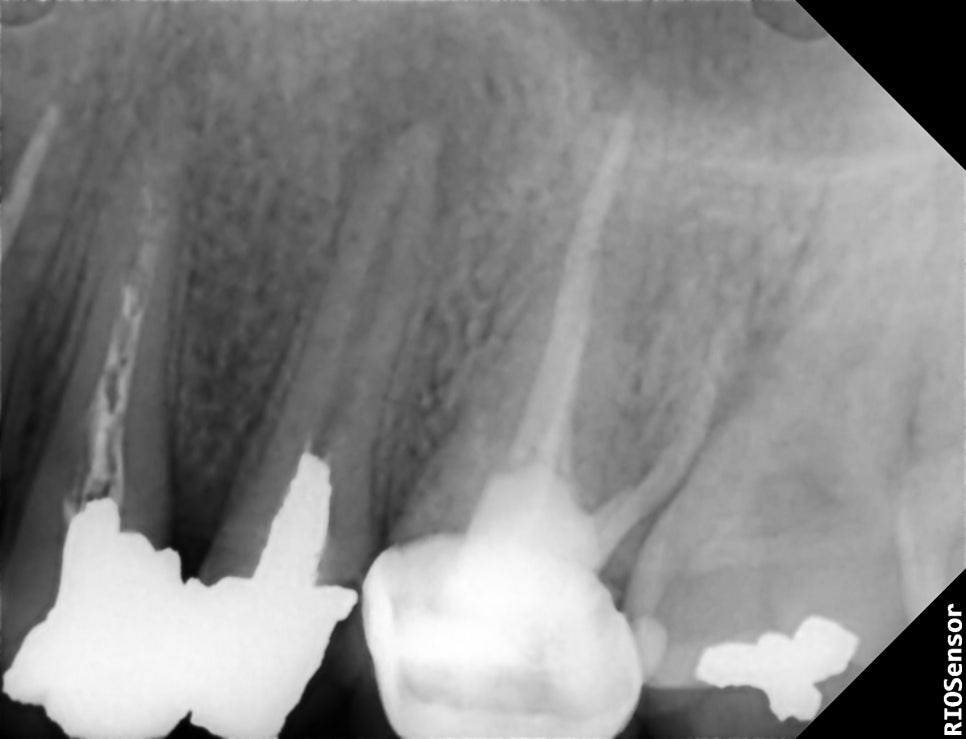

△ 초진 PA

24, 25에 엔도가 되어있...?고, 수복도 되어있었는데, 25번에 보철이 탈락되어 다시 만들고싶다고 온 환자였다.

원장님께서는 이런저런 주의사항을 환자에게 일러주고 25를 다듬고 다시 골드크라운을 제작해주셨다.

내가 '이게 뭐지'하는 생각으로 x-ray사진을 계속 보고 있으니, 원장님께서 시간이 나셨는지 오셔가지고는 한마디 해주셨다.

그 말을 듣고 대충 왜 그런지 감은 왔는데, 원장님께서 더 정확하게 말씀을 해주셨다.

위의 경우처럼 오래전에 디펄핀으로 tomy만 된 치아의 경우에 이렇게 병소가 잡히고 증상이 없는 경우가 많다고도 덧붙여주셨다.